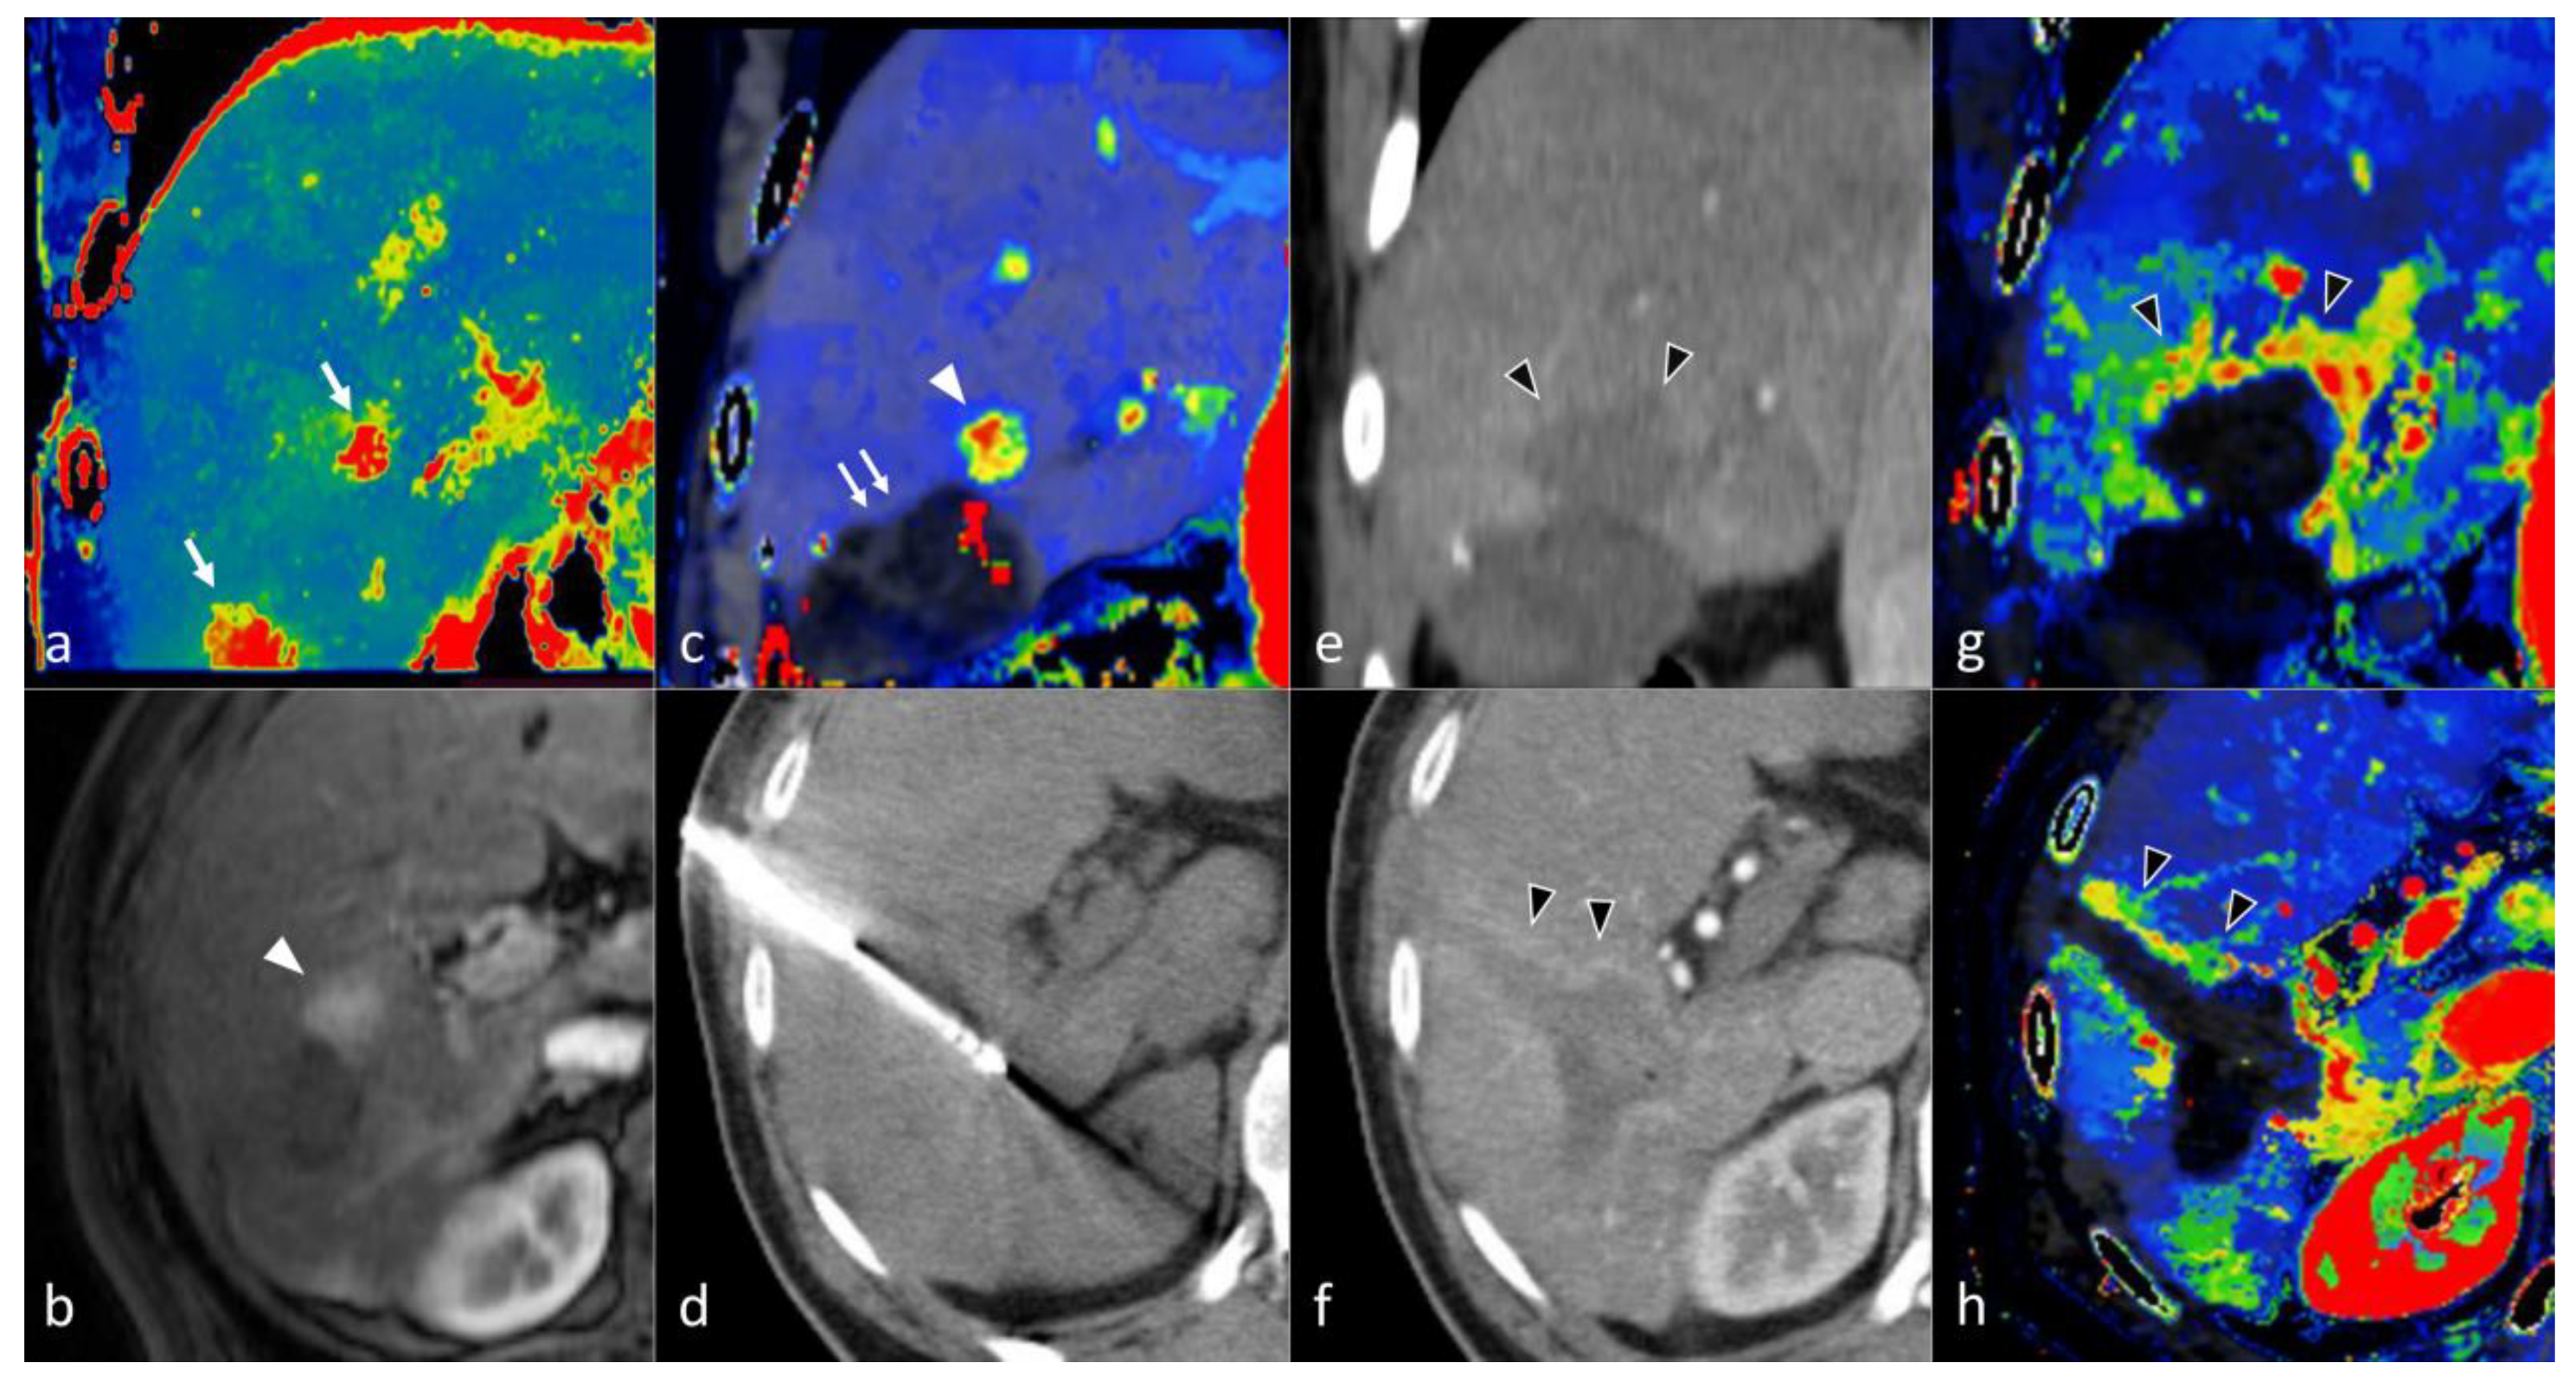

- Ippolito, D.; Pecorelli, A.; Querques, G.; Drago, S.G.; Maino, C.; Franzesi, C.T.; Hatzidakis, A.; Sironi, S. Dynamic Computed Tomography Perfusion Imaging: Complementary Diagnostic Tool in Hepatocellular Carcinoma Assessment from Diagnosis to Treatment Follow-up. Acad. Radiol. 2019, 26, 1675–1685. [Google Scholar] [CrossRef]

- Hatzidakis, A.; Perisinakis, K.; Kalarakis, G.; Papadakis, A.; Savva, E.; Ippolito, D.; Karantanas, A. Perfusion-CT analysis for assessment of hepatocellular carcinoma lesions: Diagnostic value of different perfusion maps. Acta Radiol. 2019, 60, 561–568. [Google Scholar] [CrossRef]

- Fischer, M.A.; Marquez, H.P.; Gordic, S.; Leidner, B.; Klotz, E.; Aspelin, P.; Alkadhi, H.; Brismar, T.B. Arterio-portal shunts in the cirrhotic liver: Perfusion computed tomography for distinction of arterialized pseudolesions from hepatocellular carcinoma. Eur. Radiol. 2017, 27, 1074–1080. [Google Scholar] [CrossRef]

- Borgheresi, A.; Gonzalez-Aguirre, A.; Brown, K.T.; Getrajdman, G.I.; Erinjeri, J.P.; Covey, A.; Yarmohammadi, H.; Ziv, E.; Sofocleous, C.T.; Boas, F.E. Does Enhancement or Perfusion on Preprocedure CT Predict Outcomes After Embolization of Hepatocellular Carcinoma? Acad. Radiol. 2018, 25, 1588–1594. [Google Scholar] [CrossRef] [PubMed]

- Marquez, H.P.; Puippe, G.; Mathew, R.P.; Alkadhi, H.; Pfammatter, T.; Fischer, M.A. CT Perfusion for Early Response Evaluation of Radiofrequency Ablation of Focal Liver Lesions: First Experience. Cardiovasc. Interv. Radiol. 2017, 40, 90–98. [Google Scholar] [CrossRef]

- Ippolito, D.; Bonaffini, P.A.; Capraro, C.; Leni, D.; Corso, R.; Sironi, S. Viable residual tumor tissue after radiofrequency ablation treatment in hepatocellular carcinoma: Evaluation with CT perfusion. Abdom. Imaging 2013, 38, 502–510. [Google Scholar] [CrossRef] [PubMed]